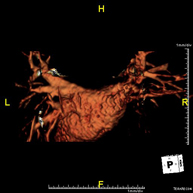

Prova diagnòstica no invasiva que consisteix en l'obtenció d'imatges d'alta definició anatòmica de les artèries cerebrals mitjançant l'ús d'un camp electromagnètic i ones de ràdio (com un emissor i un receptor). No utilitza radiació ionitzant. En la majoria dels casos és necessari l'us de contrast paramagnètic (Gadolino). Permet un estudi angiogràfic no invasiu gràcies a la injecció de Gadolino amb una reconstrucció posterior en 2D i 3D gràcies a estacions de treball especialitzades. Indicacions: malformacions vasculars, aneurismes d'artèries cerebrals, arteriosclerosi. - Angio-RM de troncs supraaòrtics

Prova diagnòstica no invasiva que consisteix en l'obtenció d'imatges d'alta definició anatòmica de les artèries caròtides i vertrebrals a nivell de coll mitjançant l'ús d'un camp electromagnètic i ones de ràdio (com un emissor i un receptor). No utilitza radiació ionitzant. En la majoria dels casos és necessari l'us de contrast paramagnètic (Gadolino). Permet un estudi angiogràfic no invasiu gràcies a la injecció de Gadolino amb una reconstrucció posterior en 2D i 3D gràcies a estacions de treball especialitzades. Indicacions: problemes circulatoris cerebrals, síncope. - RM espectroscòpia cerebral

Prova diagnòstica no invasiva que consisteix en l'obtenció d'imatges d'alta definició anatòmica de les artèries cerebrals mitjançant l'ús d'un camp electromagnètic i ones de ràdio (amb un emissor i un receptor). No utilitza radiació ionitzant. En la majoria dels casos és necessari l'ús de contrast paramagnètic (Gadolini). Permet un estudi angiogràfic no invasiu gràcies a la injecció de Gadolini amb posterior reconstrucció en 2D i 3D, gràcies a estacions de treball especialitzades. Indicacions: malformacions vasculars, aneurismes d'artèries cerebrals i arteriosclerosi. - Angio-RM de Troncs supraaòrtics

Prova diagnòstica no invasiva que consisteix en l'obtenció d'imatges d'alta definició anatòmica de les artèries caròtides i vertebrals a nivell de coll mitjançant l'ús d'un camp electromagnètic i ones de ràdio (amb un emissor i un receptor). No utilitza radiació ionitzant. En la majoria dels casos és necessari l'ús de contrast paramagnètic (Gadolini). Permet un estudi angiogràfic no invasiu gràcies a la injecció de Gadolini amb posterior reconstrucció en 2D i 3D, gràcies a estacions de treball especialitzades. Indicacions: problemes circulatoris cerebrals i síncope. - Angio-RM d'Aorta Toràcica